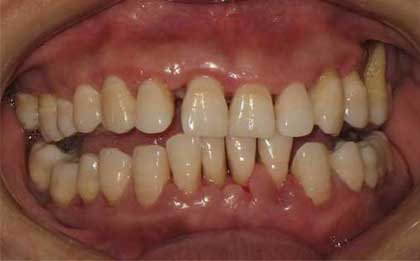

牙周炎是累及四种牙周支持组织(牙龈、牙周膜、牙槽骨和牙骨质)的慢性感染性疾病,往往引发牙周支持组织的炎性破坏。如果不治疗任其发展,终导致牙齿松动脱落。那么重度牙周炎怎么治疗?下文为大家揭晓重度压住炎的治疗方法。